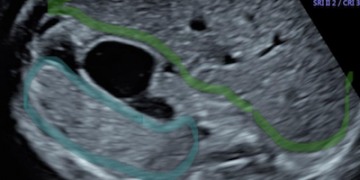

Leggi di piùCari colleghi, vi presentiamo la guida al counseling di Aprile 2025 sulla Trasposizione completa delle Grandi Arterie. Potrete scaricarla cliccando sul link. Grazie a Mariana Rita Catalano! ...